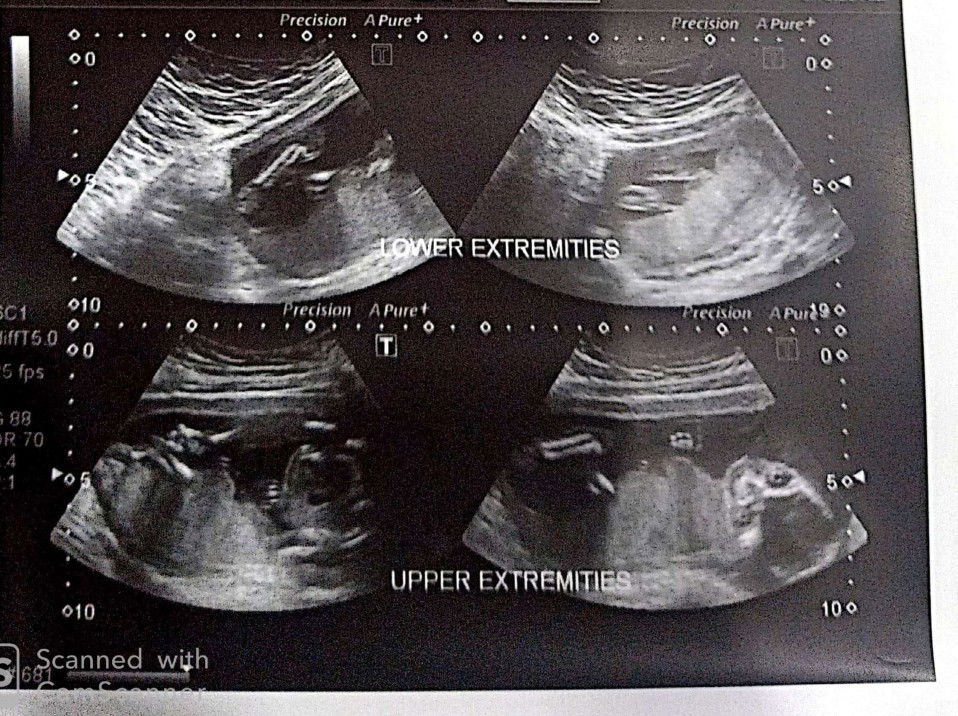

19weeks & 3days